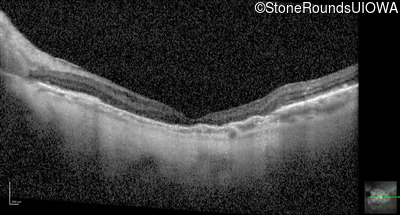

Optical Coherence Tomography - Right - 20/20 -1

Exemplar / OCT Stack